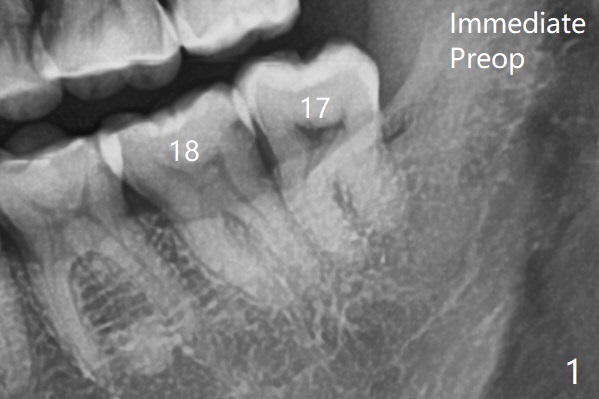

There is limited bone between the lower 2nd and 3rd molars (Fig.1).  Purchase point is made buccal to #17 for elevation.